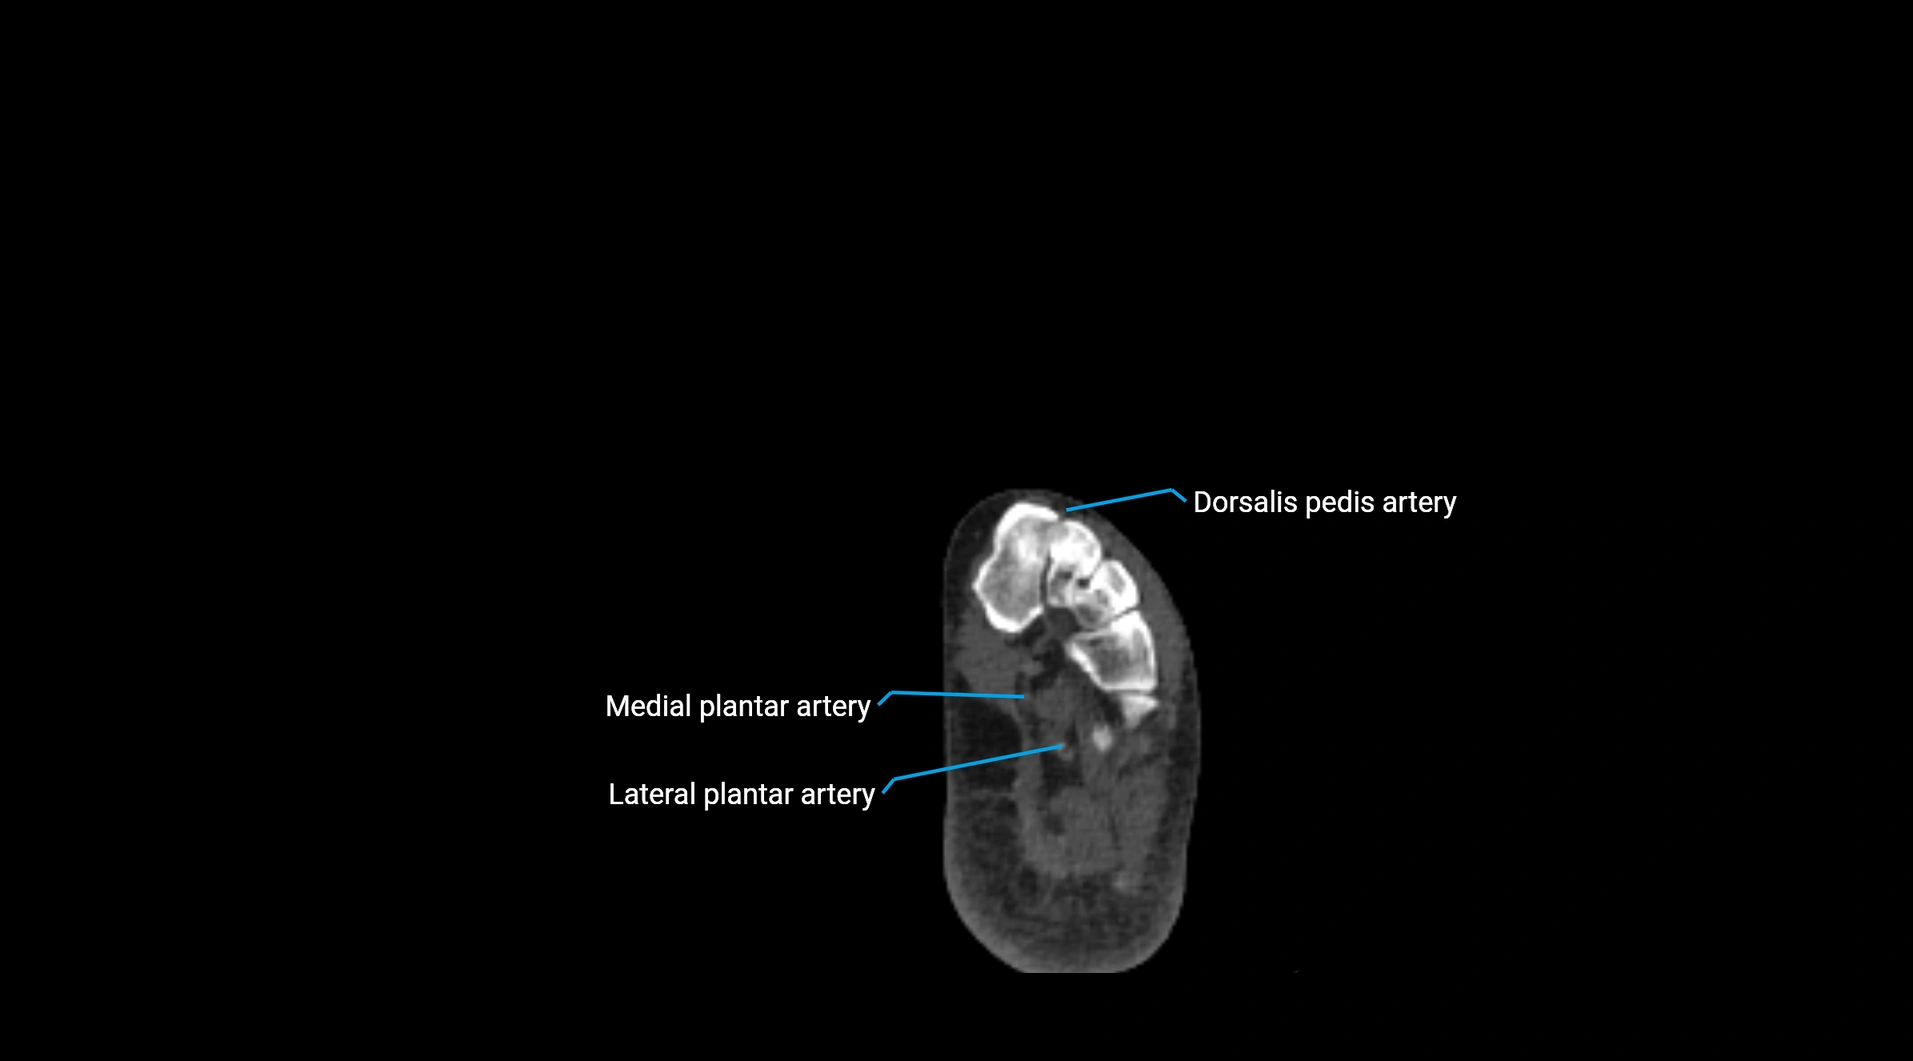

CT Appearance

Non-contrast CT:

• Appears as a tubular soft tissue structure anterior to vertebral bodies

• Calcified atherosclerotic plaques appear as hyperdense foci along the wall

• Useful for screening abdominal aortic aneurysm (AAA) size and mural calcification

Contrast-enhanced CT (CTA):

• Gold standard for abdominal aortic imaging

• Provides excellent detail of lumen, wall, aneurysm, thrombus, and branch vessels

• Multiplanar and 3D reconstructions help in aneurysm measurement, stent graft planning, and dissection evaluation

• Detects acute rupture, traumatic injury, or occlusion with high sensitivity